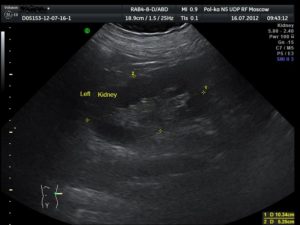

Периодически у пациентов при ультразвуковом исследовании почек выявляют некоторую выпуклость их контура — горб. Чаще всего такая патология присуща для левого органа. Однако это лишь особенность его строения и ничего более.

Такой контур никак не нарушает его работу и не влияет на качество жизни его владельца. Этот вид патологии вносят в протокол УЗИ как «горбатая почка».

Причинами такого формирования почек становится аномалия при развитии эмбриона или позднее при давлении селезенки на орган.